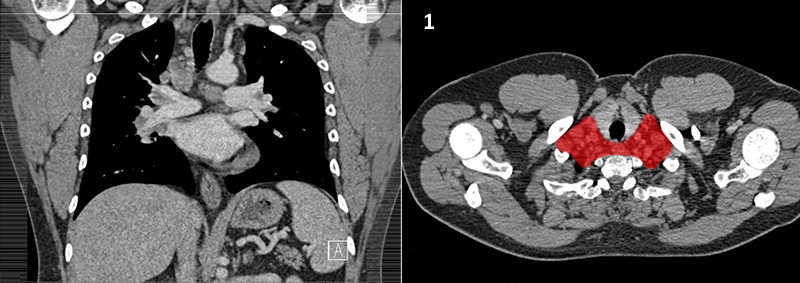

Nodal zones and stations according to the International Association for the Study of Lung Cancer (IASLC) node map.

Table (above): Nodal zones and stations according to the International Association for the Study of Lung Cancer (IASLC) node map. (Source: 1,2) *Depends on the side of the tumour.